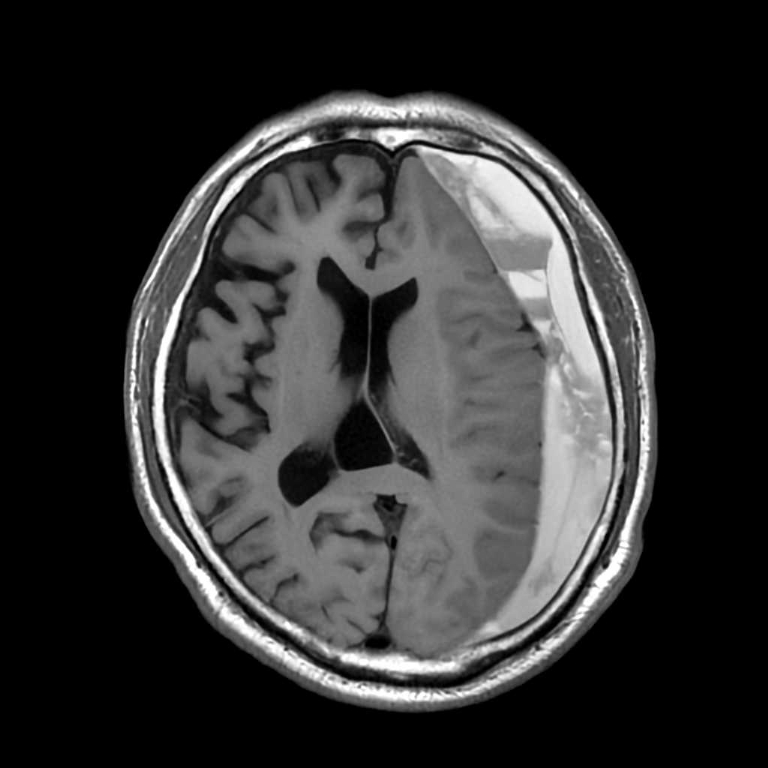

頭部

脳梗塞

脳動脈瘤

硬膜下血腫